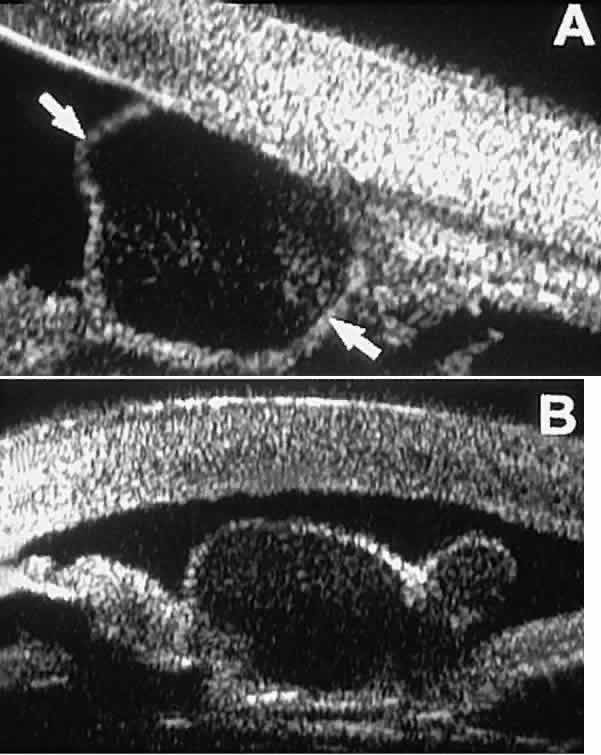

Solid iridociliary tumors present variable internal reflectivity depending on tumor type.14 Most solid lesions that occur on the iris are nevi. Benign nevi of the iris and ciliary body usually appear on UBM as relatively small hyporeflective lesions replacing a part or all of the underlying uveal stroma locally (Fig. 26). Such lesions usually do not destroy the underlying neuroepithelium of the iris or ciliary body, extend intrasclerally, or have prominent intralesional blood vessels.

Fig. 26. UBM features of iris nevi. A. Superficial nevus appears as hyper-reflective layer of iris (white arrow). Normal iris stroma (dark arrow) is more sonolucent. B. Fusiform nevus of peripheral iris occupying full thickness of iris stroma (arrow). Note intact iris pigment epithelium underlying lesion.

In contrast, malignant melanomas of the iris and ciliary body are much less common. On UBM, such tumors are usually larger than benign nevi, and they are more likely to have caused focal or extensive disruption of the adjacent neuroepithelial layers, to have invaded the sclera, and to be associated with prominent intralesional blood vessels (Fig. 27). Some malignant melanomas of the ciliary body and most ciliochoroidal melanomas are too large in basal diameter to be fully revealed in a single UBM image, and many of these lesions are also too thick to be measured by this technology. In the case of a melanocytic tumor of the iris or ciliary body that is not clearly either a benign nevus or a malignant melanoma, serial UBM evaluations may prove useful for assessing the tumor's growth and other changes that might warrant either biopsy or complete excision of the mass.

Fig. 27. UBM features of malignant melanoma of iris. (A) Iridociliary melanoma replacing peripheral iris and ciliary body and filling anterior chamber angle. Mass is slightly sonolucent compared with normal iris stroma. (B) Larger iridociliary melanoma. Iris appears to arise from side of mass.